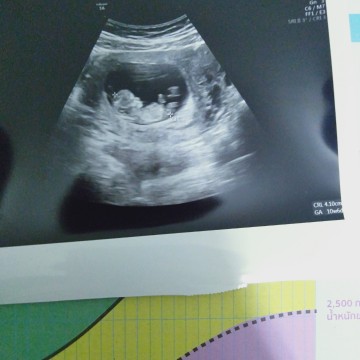

11wค่ะ

Post reply image